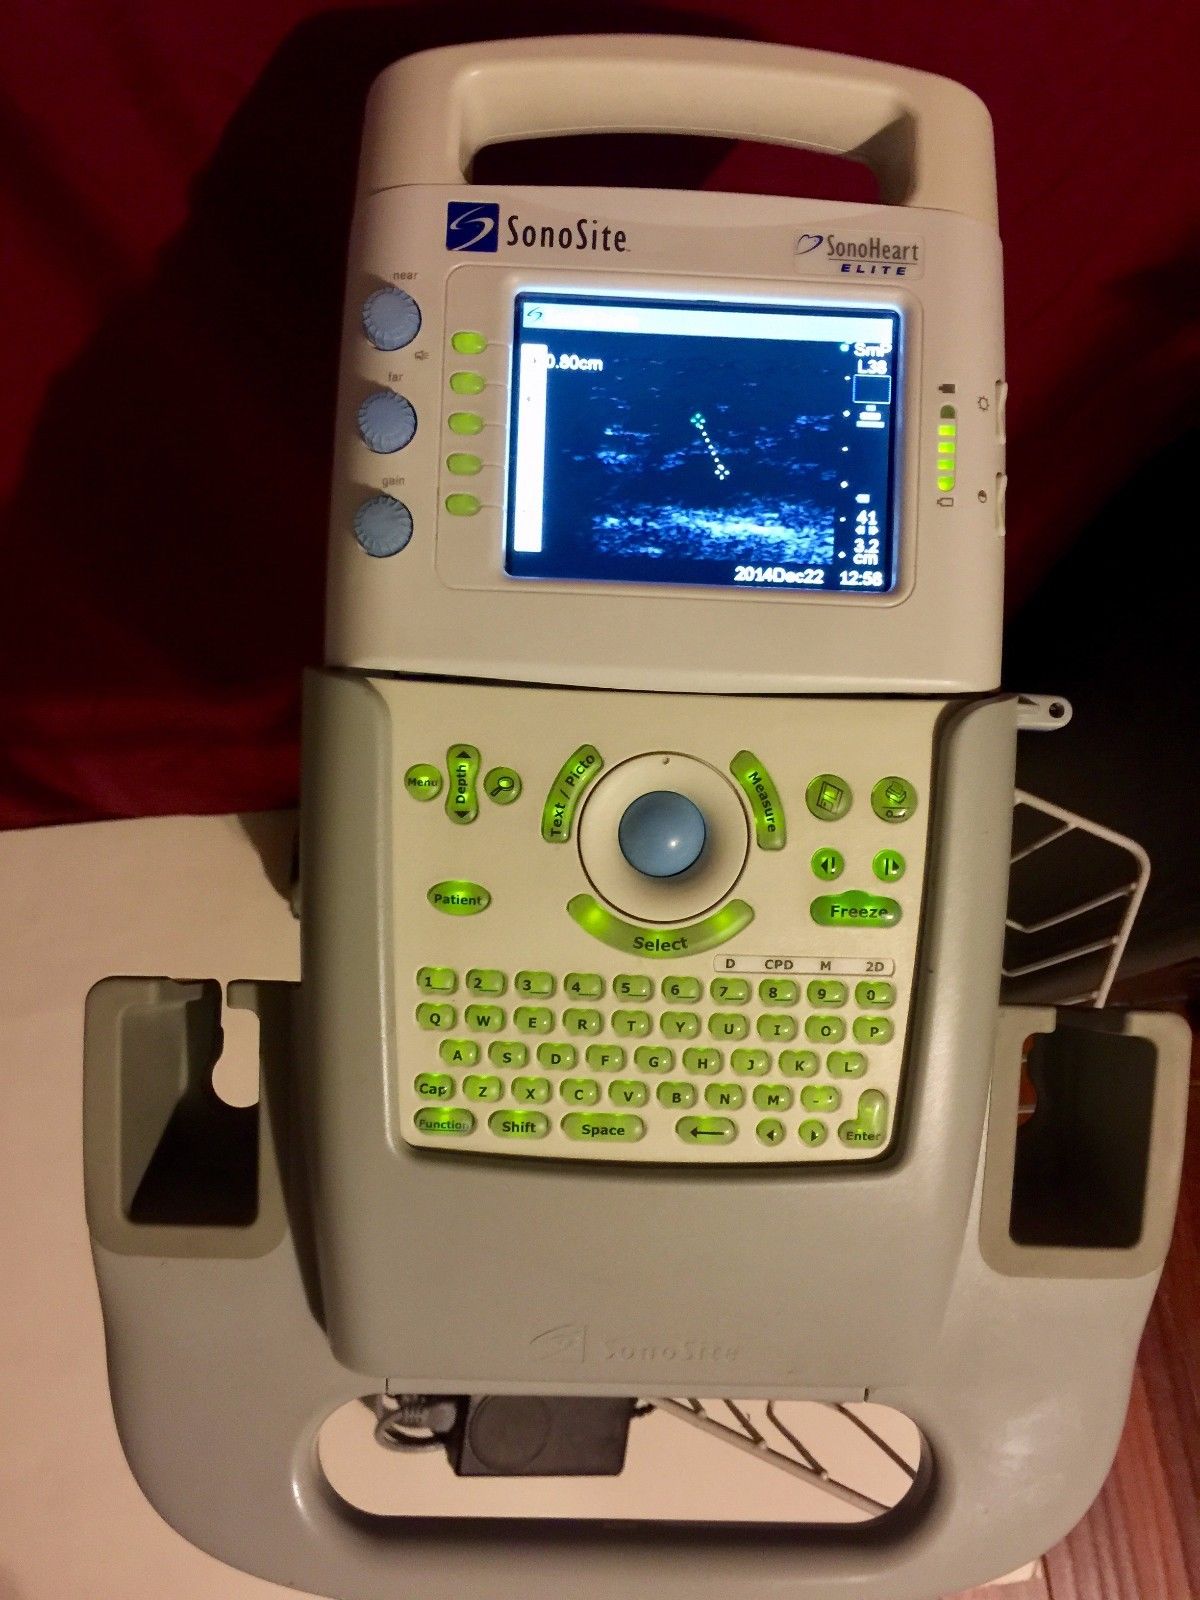

SONOSITE Ultrasound Sonoheart Elite With Cart

Sale price$ 9,590.70